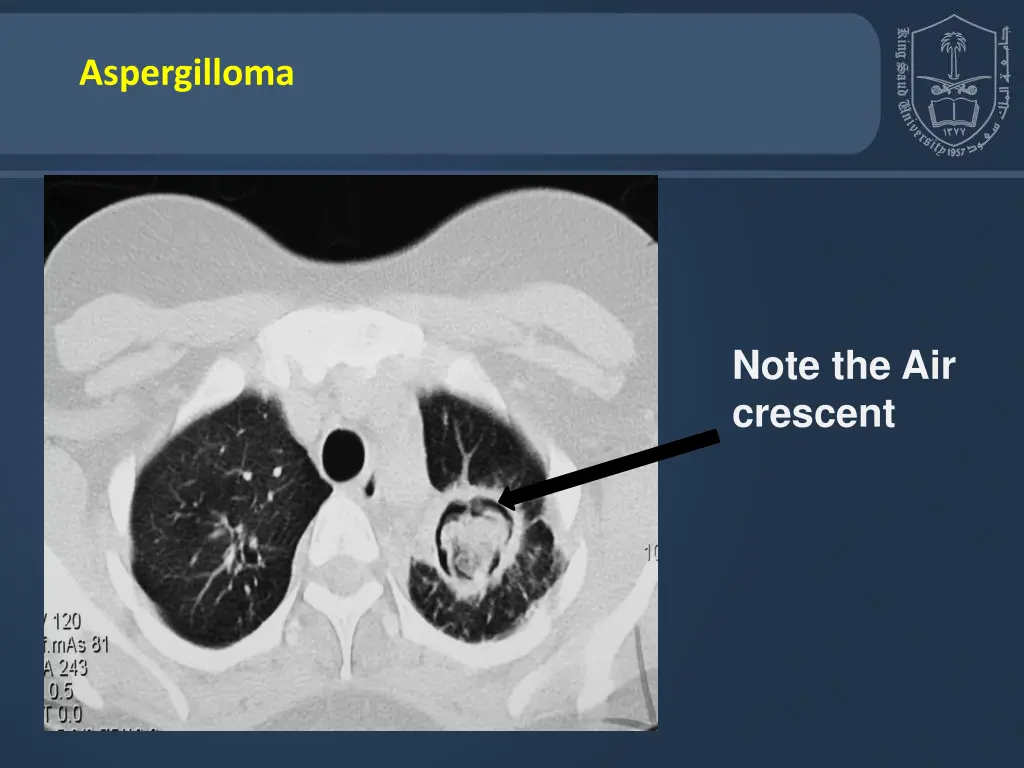

10. Aspergilloma Note the Air crescent

8. Aspergillosis Chronic Aspergillosis (Colonizing aspergillosis) (Aspergilloma OR Aspergillus fungus ball) Signs include: Cough, hemoptysis, variable fever Radiology will show mass in the lung , radiolucent crescent Invasive pulmonary Aspergillosis Signs: Cough , hemoptysis, fever, Leukocytosis Radiology will show lesions with halo sign